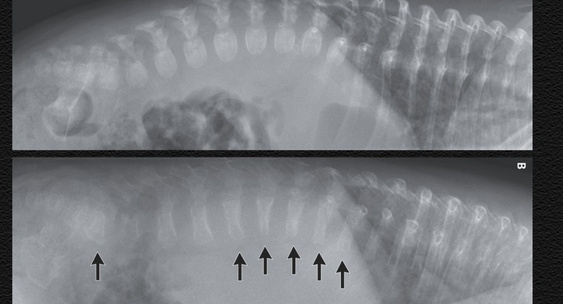

На повторной рентгенограмме позвоночника также обнаружили выраженное снижение костной массы и компрессионные переломы позвонков.Главный региональный